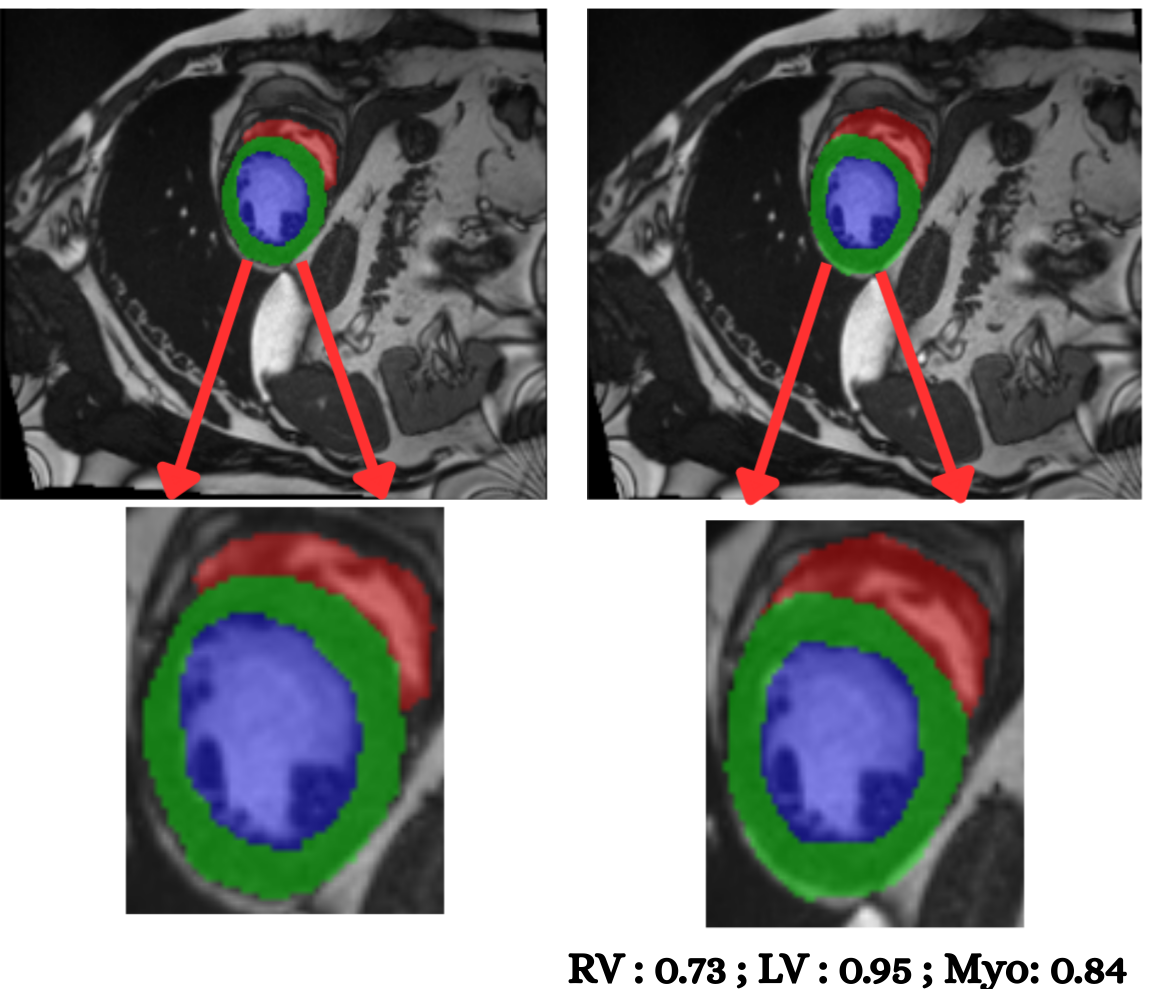

Figure 8 illustrates segmentation outputs on the M&Ms (Multi-Centre, Multi-Vendor) cine-MRI dataset, which exhibits both contrast variation and vendor–specific acquisition differences compared to ACDC. The model retains consistent ventricular geometry, recovering LV and Myocardium structure without retraining, mirroring the zero-shot Dice performance of 74.8% (Table 11). Boundary thickness remains physiologically accurate, with only minor degradation in the right ventricle, an expected behaviour under cross-domain shifts and also reflected quantitatively in the ablation-driven robustness improvements from normalization and loss design. These results demonstrate that PULSE does not overfit to a single scanner distribution but instead transfers cardiac structure priors across unseen clinical environments.